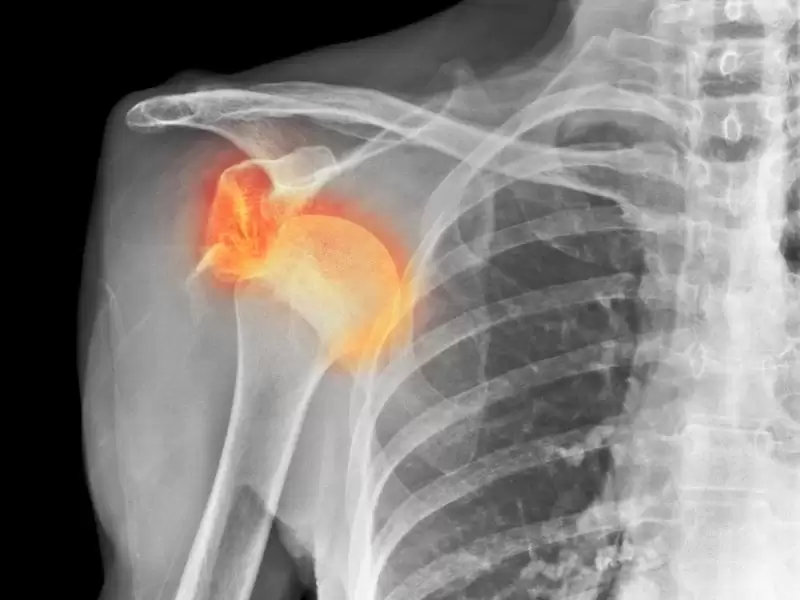

Omuz sıkışma hastalığı rotator manşetin ve bursa denilen keseciğin omuz başı ile akromion denilen omuz çatısı arasında sıkışmasıdır. Orta yaşlardan itibaren görülen, sporcular, endüstri işçileri, ev bakım elemanlarında daha sık görülen bir sorundur. Anatomik yapı problemleri nedeniyle 20 li yaşlarda da görülebilir.

Ana tanı muayene ile konur. Direkt grafiler (AP, skapula Y, axiller) ve MR ile sıkışma nedeni, tendonların durumu netleşir ve tedavi planlanır.